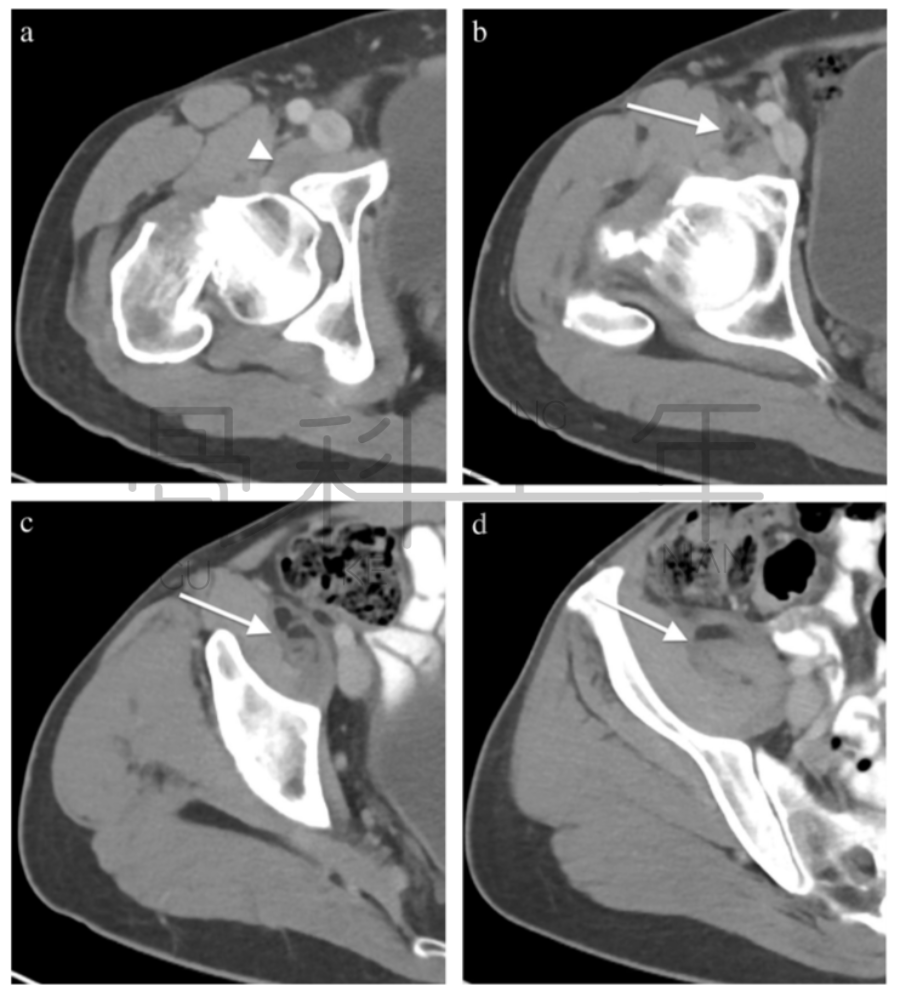

病例6 一例82岁髋部外伤患者,非移位股骨颈骨折,在CT横断面可见积脂血症,MR证实股骨颈骨折。关节积脂血症在非移位股骨颈骨折的识别中作用明显。